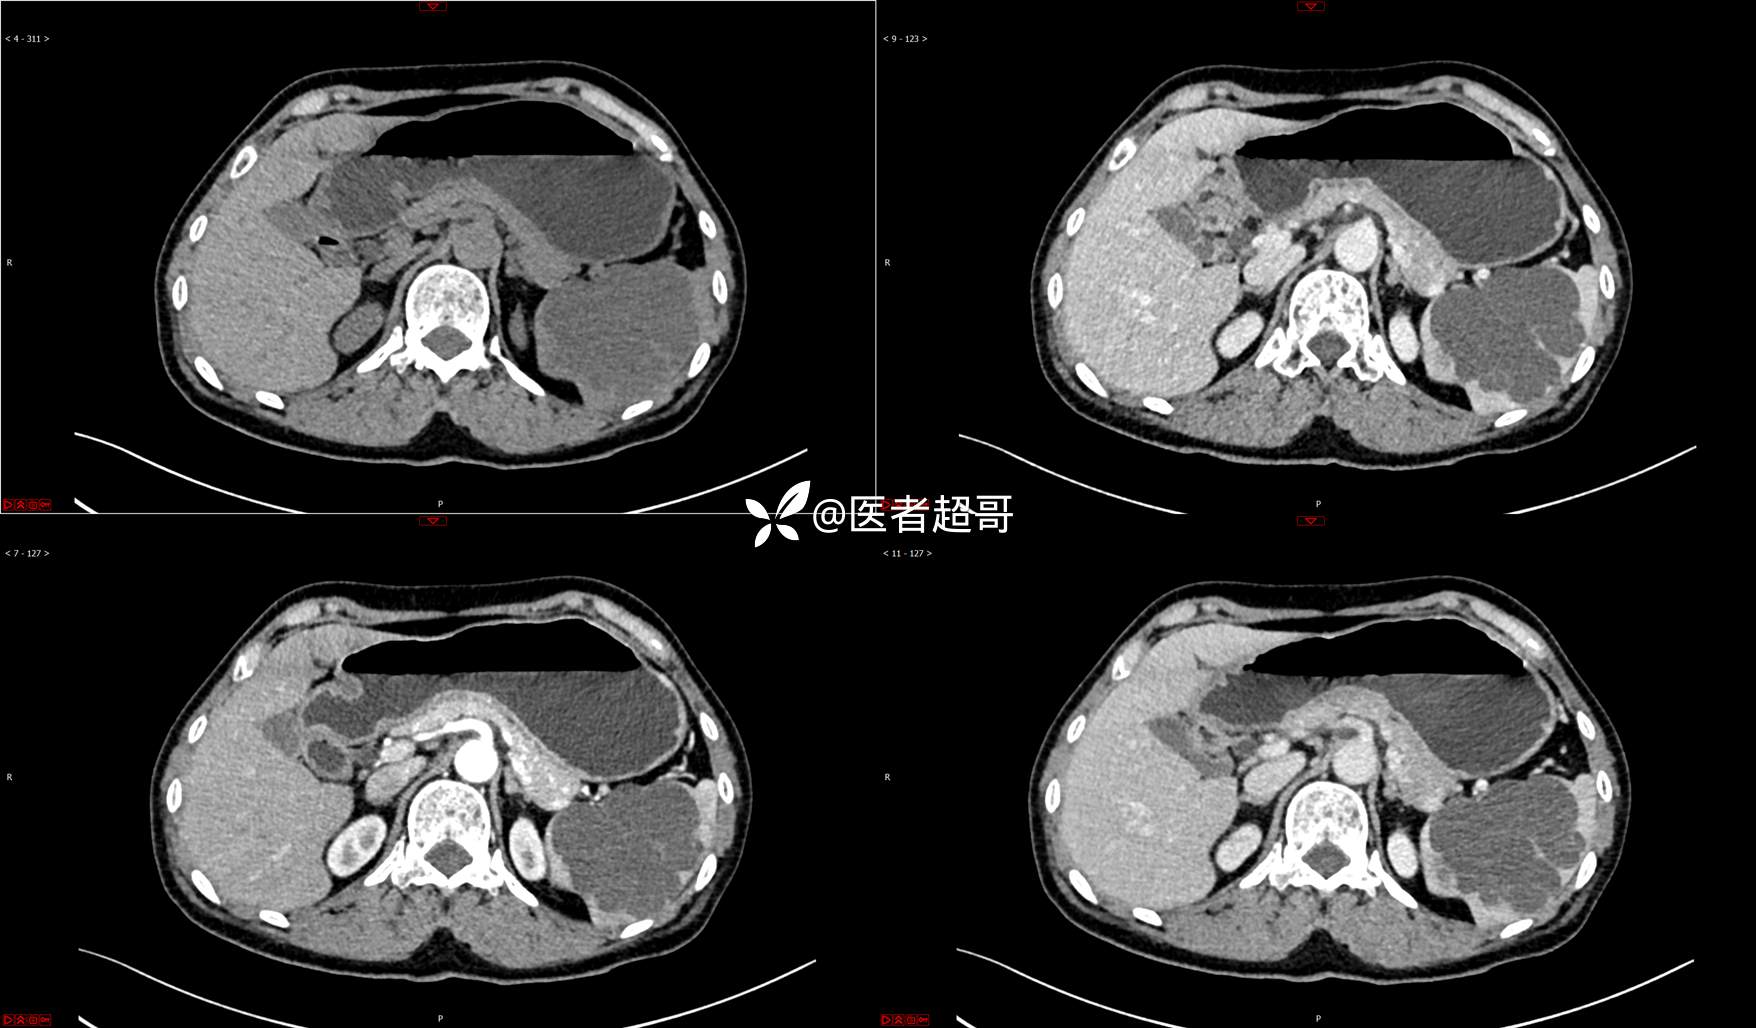

【影诊笔记739】脾脏囊性占位,查体偶发,请赏析,有病理!

女,6岁 0201215 02

主 诉:查体发现脾脏囊性占位4年。

现病史:患者4年前于人民医院查体时发现脾脏囊性占位。-04-20到我院复查,行上腹平扫+强化CT示:肝囊肿,脾脏囊实性占位,囊腺瘤?当时无明显症状,未行任何治疗。4个月前无明显原因及诱因开始偶尔出现左上腹疼痛,为隐痛,伴腰部放射痛,无腹胀、腹泻,无恶心、呕吐,无发热、畏寒、全身乏力,无胸痛、胸闷等其它不适。在外未行特殊治疗,今为求进一步诊治来我院就诊,行腹部彩超(肝、胆、胰、脾、肾)示:脾脏房囊性肿物。门诊以“脾占位性病变”收入院。发病以来,患者神志清楚,精神可,饮食可,睡眠欠佳,大小便正常,近期体重无明显变化。